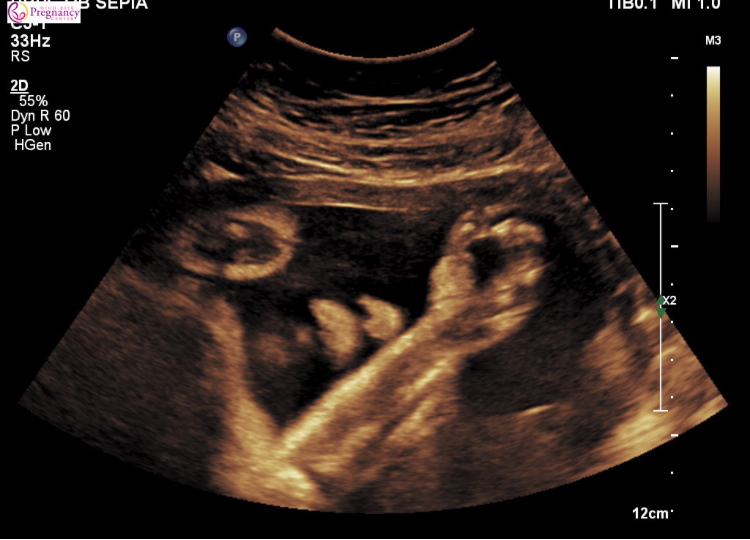

32 week scan went well. Things looking good but baby’s head and abdomen are measuring 4 weeks ahead at 36 weeks!! Limbs are on track. Estimated weight is 4 lbs 9oz or 72% percentile. Oye ve!! My vagina weeps. Little one also didn’t cooperate and didn’t show her face so no good 3D pics, but this cute one with her hand/arm in front of her face. Maybe she’s embarrassed we’re already commenting on her weight. Lol

@northbeach3 - glad your scan went well! I'm excited for my 32 week scan in a few weeks. She's already practicing her drama queen posture